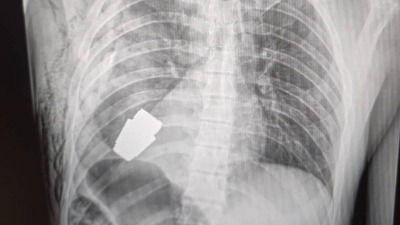

Ukraynalı bir askerin vücuduna saplanan patlamamış bir el bombası, cerrahların müdahalesiyle başarılı bir şekilde çıkarıldı.

Newsweek'te yer alan habere göre, Ukrayna Savunma Bakan Yardımcısı Hanna Maliar, sosyal medya hesabında cerrahı ve röntgenin fotoğrafını bir açıklamayla paylaştı.

Maliar, doktorların patlamamış bir VOG el bombasını askerin vücudundan çıkarmak için sağlık personelinin güvenliğini sağlamakla görevli iki istihkam erinin de bulunduğu bir operasyon gerçekleştirildiğini söyledi.

Maliar, el bombasının her an patlayabileceği için ameliyatın elektrokoagülasyon yapılmadan gerçekleştirildiğini ve operasyonu Ukrayna Silahlı Kuvvetleri'nin en deneyimli cerrahlarından biri olan Andrew Willow tarafından gerçekleştirildiğini dile getirdi.

Cerrahi müdahalenin başarılı olduğunu ve yaralı askerin iyileşme sürecinde olduğunu aktaran Maliar, el bombasının askerin göğsüne ne zaman ve nasıl saplandığının net olarak bilinmediğini ifade etti.